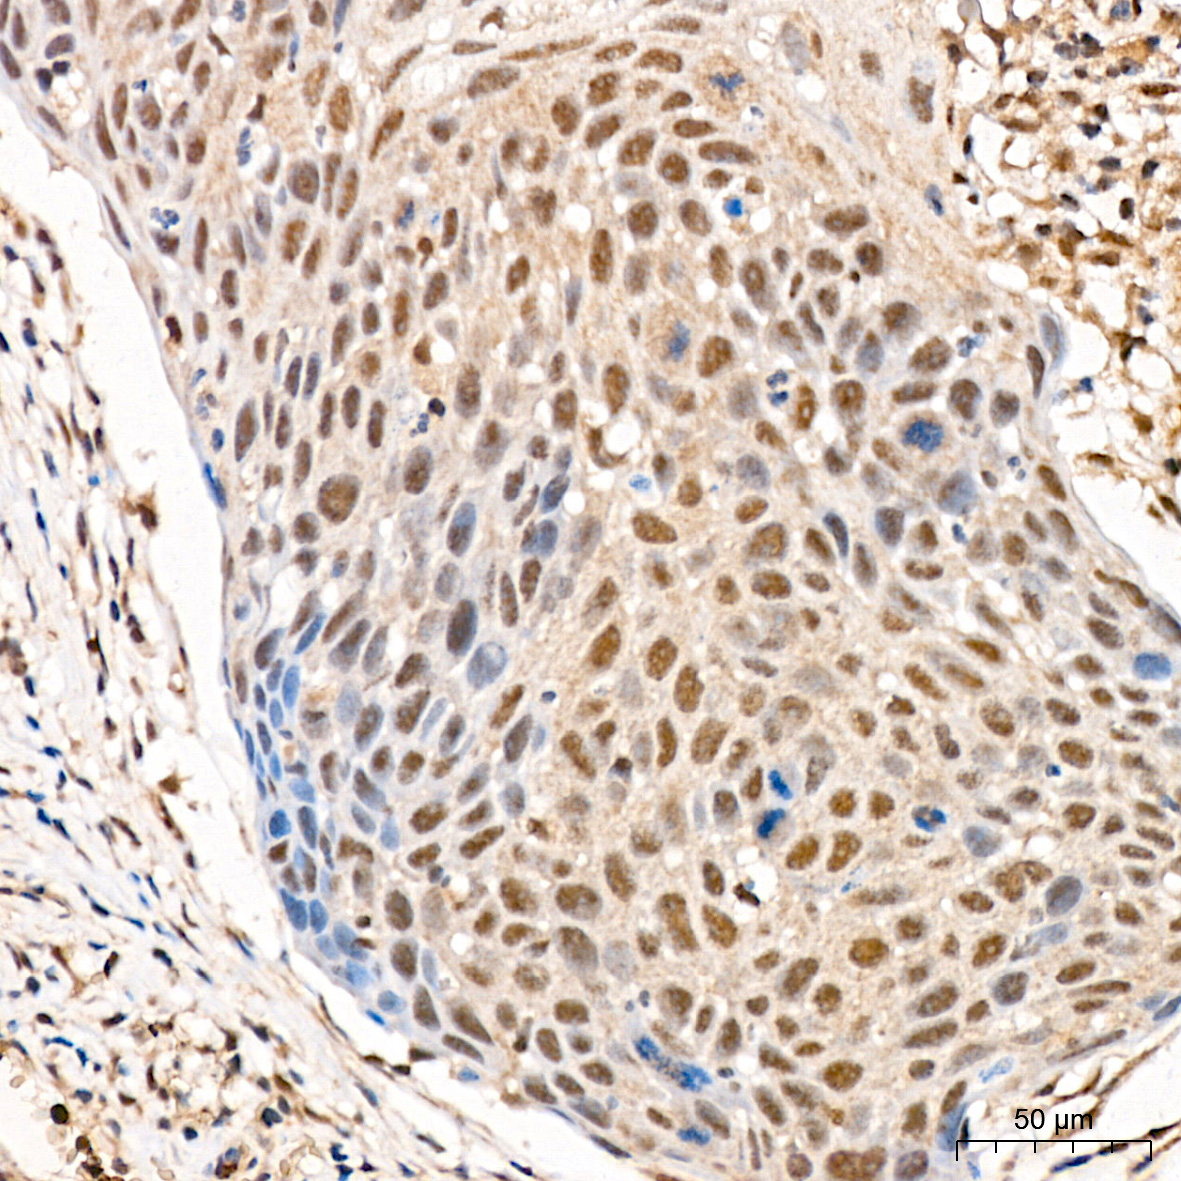

肿瘤细胞增殖是肿瘤细胞在体内或体外不断分裂和增加其数量的过程。正常情况下,细胞增殖是组织生长和修复的正常生理过程,但当细胞失去正常的生长调控机制,可能导致异常的细胞增殖,形成肿瘤。

肿瘤细胞是在基因水平上以不受控制的方式生长和分裂,侵入正常组织和器官并最终扩散到全身。这些细胞在代谢、形态、功能上与其来源的正常细胞或多或少的不同。肿瘤细胞增殖与异位受体或激酶(如 Bcr-Abl、EGFR、HER2、c-Met 和 Raf),组成型激活信号转导通路(如 PI3K/Akt 通路、MAPK 通路、Wnt 通路、Hippo 通路)和转录调节剂(c-myc、Smads、STATs、YAP)有关。